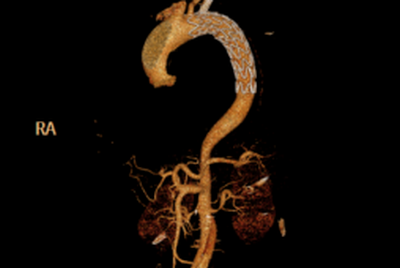

血管外科王颖主治医师通过了解患者病史,得知体态肥胖的他5年前血压竟然高达200/120mmHg,但以自己没有任何症状为理由拒绝服用药物,并且再未规律监测血压。在进一步主动脉CTA检查后,结果印证了之前的判断:典型的胸主动脉夹层(Stanford B型)。幸运的是,病变没有导致内脏、四肢及颈部血管的急性缺血。

由于情况危急,患者收治入院后即下达病危通知书,通过严格控制血压(收缩压维持在100-120mmHg)及心室率(60-70次/分),患者的疼痛症状很快得到缓解。在副院长王兵教授和血管外科崔文军主任的指导下快速制定手术方案,尽快拆除这枚“不定时炸弹”。通过仔细研判CTA结果,考虑到患者相对年轻,为了降低远期缺血性并发症,王兵教授决定采用目前先进的手术方式之一,即体内原位开窗,重建左侧锁骨下动脉。

▲ 支架植入前造影